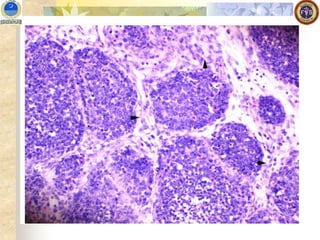

Microscopic Lesions

◼ Marked lymphoid follicles necrosis with heterophils rich

cellular infiltrates, edema and hyperemia followed by atrophy

and Interfollicular fibroplasia

◼ Starts at medullary region and soon lymphocytes are

replaced by heterophils, pyknotic debris, and hyperplasic

reticuloendothelial cells .

◼ All follicles are effected 3-4 days PI and inflammation

subsides cavities are developed in the medulla region

◼ Necrosis and phagocytosis of of plasma cells and hetrophils

◼ Initial depletion of T lymphocytes in first week followed by B

lymphocytes destruction and atrophies follicles indicate no B

cell